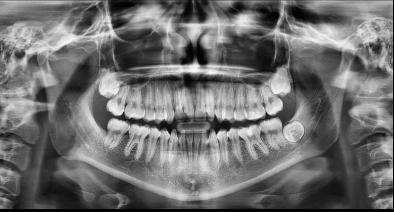

Estudios radiográficos de inicio

En la radiografía lateral de cráneo se ve la clase II esquelética, con crecimiento hiperdivergente, hiperplasia sagital maxilar y proinclinación del incisivo mandibular (Figura 6).

En la radiografía panorámica se observan 32 piezas dentales, con los terceros molares que se encuentran en estadio 6 de Nolla (Figura 7).